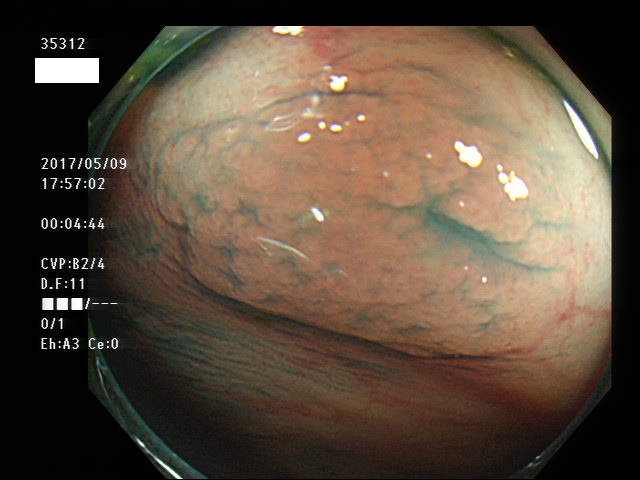

上記100名より抽出した平坦・陥凹型腺腫・SSAP(=癌化の危険が高いが見落としやすい病変)の内視鏡写真